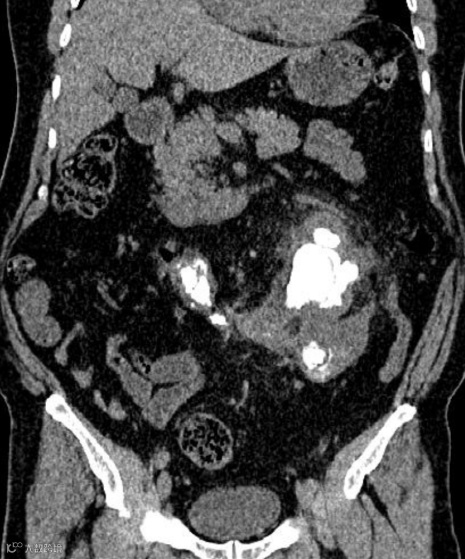

男,75岁,无痛性血尿。CT增强扫描提示马蹄肾合并肾峡部后下缘、中线左侧肿块,肿块切除后组织病理学检查显示为嗜酸细胞瘤。